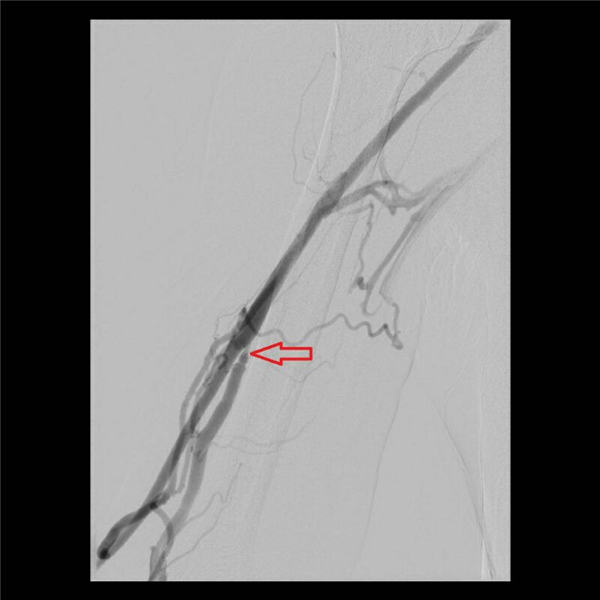

随后,两位主任通力协作,通过放置球囊扩张的方法,对血管的三处狭窄段分别用球囊扩张后,可见狭窄段部分或者完全扩张(下图红色箭头所示)。